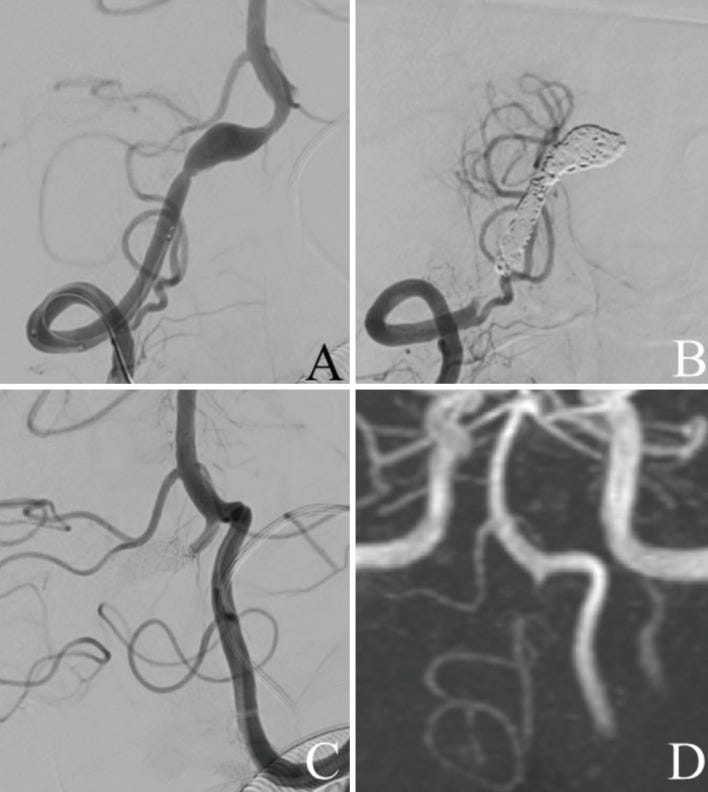

(A) Frontal view of the right vertebral artery angiography (VAG) before stent-assisted coil embolization shows dissecting aneurysm in the right vertebral artery (VA) involving the right posterior inferior cerebellar artery (PICA). (B) Frontal view of the right VAG after stent-assisted coil embolization shows coil occlusion of the aneurysmal sac and patency of the right VA and right PICA. (C) Cone beam computed tomography (CT) image shows the bladed stent placed across the dissecting lesion and coils deployed into the sac. (D) Postoperative magnetic resonance angiography (MRA) performed 2 weeks after treatment shows that the dissecting aneurysm is not visualized and the right PICA is patent.